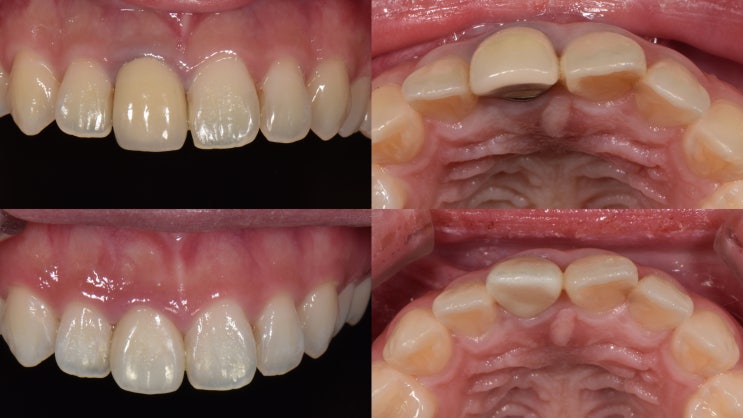

변색된 PFM 앞니 크라운 실활치 미백,전체치아 미백후 지르코니아크라운 재치료

치과의사 투쓰맨, 자주하는 앞니 크라운 재치료 방법 정리 20대 젊은 분인데, 어릴때 충치/사고등으로 부모...